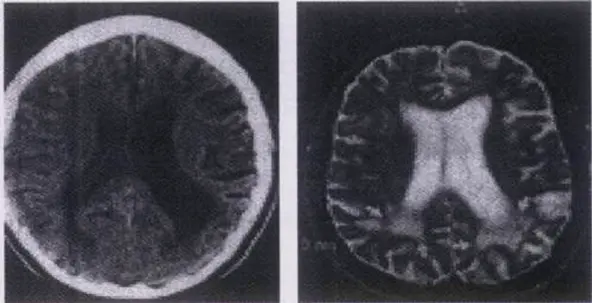

На МРТ головного мозга – перивентрикулярные диффузные изменения у пациента 56 лет с тяжелой АГ («гипертоническая лейкоэнцефалопатия» – лейкоареоз)